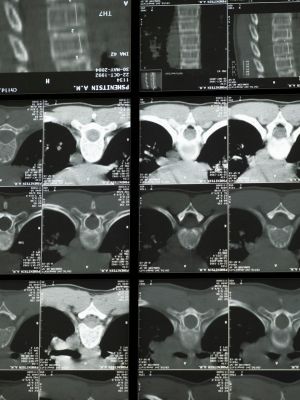

MSCT snimanje kičmeMSCT snimanje kičme

Multislajsni CT skener kičme omogućava detaljno snimanje koštanih i okolnih struktura kičmenog stuba. Snimanje se obavlja pomoću rendgenskih zraka i savremene računalne obrade, čime se dobijaju jasni preseci u tankim slojevima. Ovakav pregled pomaže u preciznom sagledavanju promena koje mogu biti uzrok bola, ograničene pokretljivosti ili neuroloških tegoba.

Tokom pregleda pacijent leži na stolu koji se lagano pomera kroz otvor aparata kružnog oblika. Neophodno je mirovanje kako bi snimci bili jasni i precizni. U pojedinim trenucima može se zatražiti kratko zadržavanje daha.